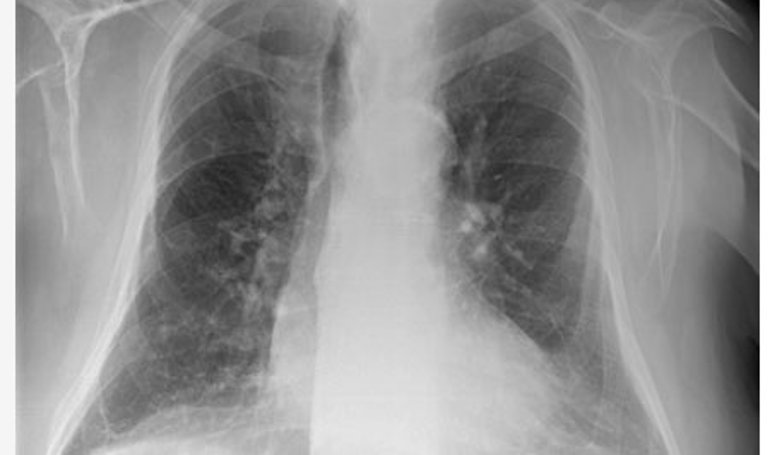

Las TC de tórax en pacientes Covid-19 muestra la eficacia de las vacunas para reducir la enfermedad

Las tomografías computarizadas (TC) ofrecen un enfoque adicional para demostrar la eficacia de las diferentes vacunas contra el Covid-19 para reducir el impacto de un diagnóstico, según un estudio realizado por investigadores italianos y publicado en el 'American Journal of Roentgenology' (AJR) que ha analizado la evaluación de los hallazgos de la TC de tórax en neumonía en estos pacientes en la pandemia.